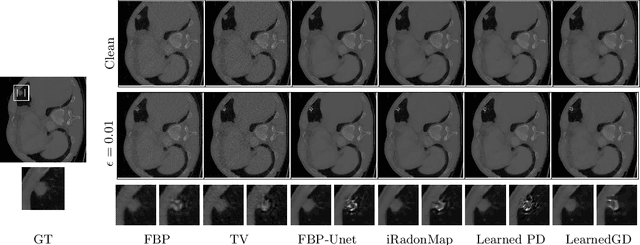

Abstract:Low dose computed tomography (CT) acquisition using reduced radiation or sparse angle measurements is recommended to decrease the harmful effects of X-ray radiation. Recent works successfully apply deep networks to the problem of low dose CT recovery on bench-mark datasets. However, their robustness needs a thorough evaluation before use in clinical settings. In this work, we evaluate the robustness of different deep learning approaches and classical methods for CT recovery. We show that deep networks, including model-based networks encouraging data consistency, are more susceptible to untargeted attacks. Surprisingly, we observe that data consistency is not heavily affected even for these poor quality reconstructions, motivating the need for better regularization for the networks. We demonstrate the feasibility of universal attacks and study attack transferability across different methods. We analyze robustness to attacks causing localized changes in clinically relevant regions. Both classical approaches and deep networks are affected by such attacks leading to changes in the visual appearance of localized lesions, for extremely small perturbations. As the resulting reconstructions have high data consistency with the original measurements, these localized attacks can be used to explore the solution space of the CT recovery problem.